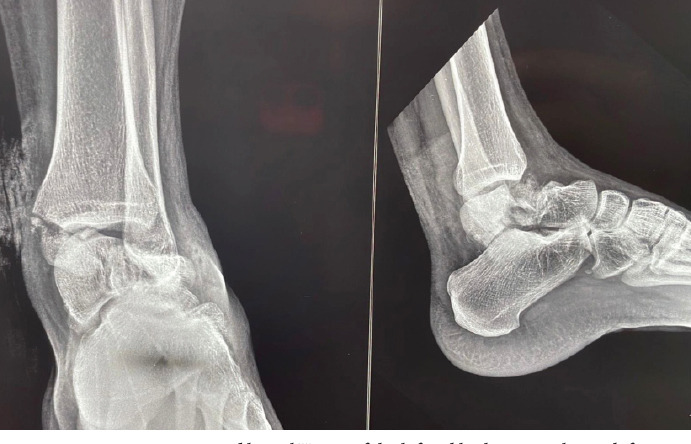

Case report: We share this unusual case of a Hawkins type-3 talus neck fracture along with a serious Grade 3B medial malleolus fracture and ankle subluxation, which was treated with cleaning the wound, realigning the ankle, and surgery to fix the bones. Post-operatively, the wound was healthy and free of infection. Despite being told to avoid weight-bearing for three months, the patient lost follow-up after a month and started occasional partial weight bearing. During the 10th post-operative week, we found a mild degree of talar neck collapse and Hawkins sign radiologically. The range of motion for the ankle was dorsiflexion of 0-15° and plantar flexion of 0-30°, with minimal swelling and pain on weight bearing.

Conclusion: This case highlights the rarity and complexity of a talar neck fracture with ipsilateral medial malleolar fracture and ankle dislocation. Positive early outcomes were achieved through timely surgery within 10 h, careful soft tissue management, and appropriate fixation. The presence of a partial Hawkins sign post-operatively indicated preserved talar vascularity and reduced risk of avascular necrosis.